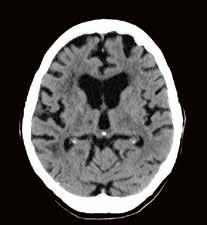

2. Vergleich eines cranialen CTs mit und ohne Deep Learning Rekonstruktion AiCE:

CTDI

30,2 mGy 544,6 mGy*cm

CCT AIDR

CCT AiCE

DVT: CDTI DLP Volumen-CT 6,5 mGy 39 mGy*cm DVT 7,3 mGy 76,6 mGy*cm Vorgänger-CT 17,1 mGy 176 mGy*cm CT vs. DVT

„AiCE unterstützt die Diagnosefindung in der Neuroradiologie dank der sofort sichtbar besseren Bildqualität bei gleicher Dosis.“